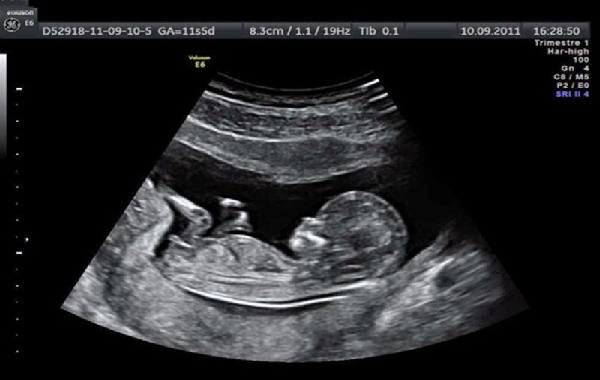

Thai nhi đạt 11-13 tuần 6 ngày tuổi là thời điểm quan trọng trong kế hoạch khám thai định kỳ của mẹ bầu. Đây là thời điểm lý tưởng để phát hiện và loại bỏ các dị tật bẩm sinh. Bác sĩ sẽ tiến hành đo độ mờ da gáy và tầm soát cấu trúc của thai nhi, đồng thời gợi ý khả năng bất thường về nhiễm sắc thể...

Ở lần khám này, mẹ bầu sẽ được chỉ định siêu âm để phát hiện các dị tật như vô sọ, hở bụng, thoát vị rốn, bất thường về xương mũi, tim, não... Ngoài ra, bác sĩ có thể tiến hành xét nghiệm máu, đo huyết áp cho mẹ bầu để tầm soát về số lượng nhiễm sắc thể bất thường và kiểm tra nguy cơ tiền sản giật.